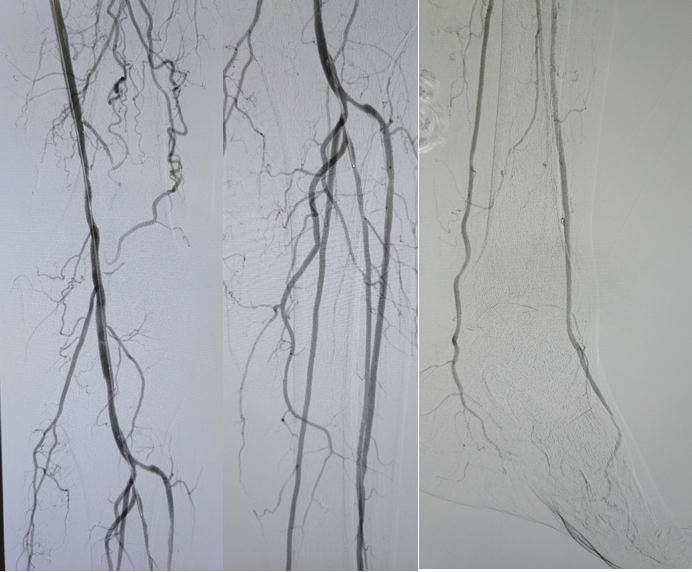

病例2(股腘动脉长段闭塞):

另一例长段闭塞病变,IVUS证实导丝真腔通过后,指导术者选择了合适尺寸的Rotarex导管进行减容,联合普通球囊(POBA)预扩及DCB治疗,获得了满意的管腔,避免了支架植入。

图:导丝通过后3mm球囊预扩

图:多处假腔通过,遂5mm球囊预扩

图:一期支架植入